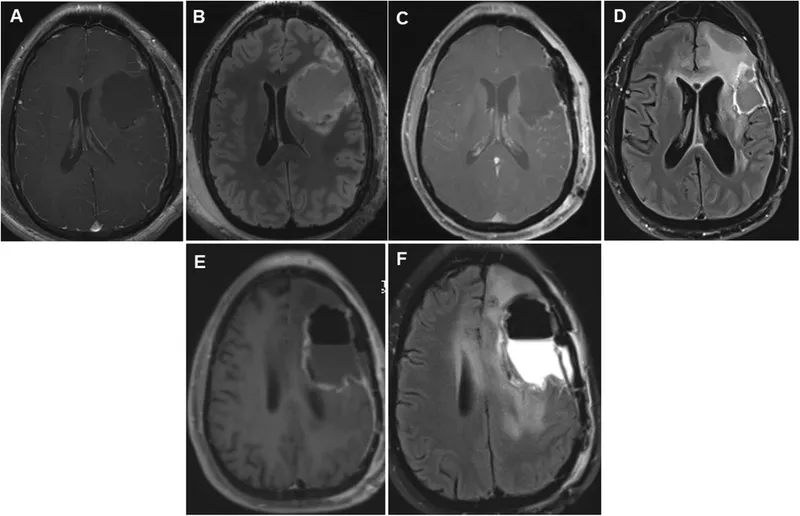

- Investigations: Recent MRI/CT. Baseline bloods (FBC, U&E, Coags).

⭐ Delayed emergence or neurological deterioration post-craniotomy mandates urgent CT scan to exclude intracranial hematoma or acute hydrocephalus.